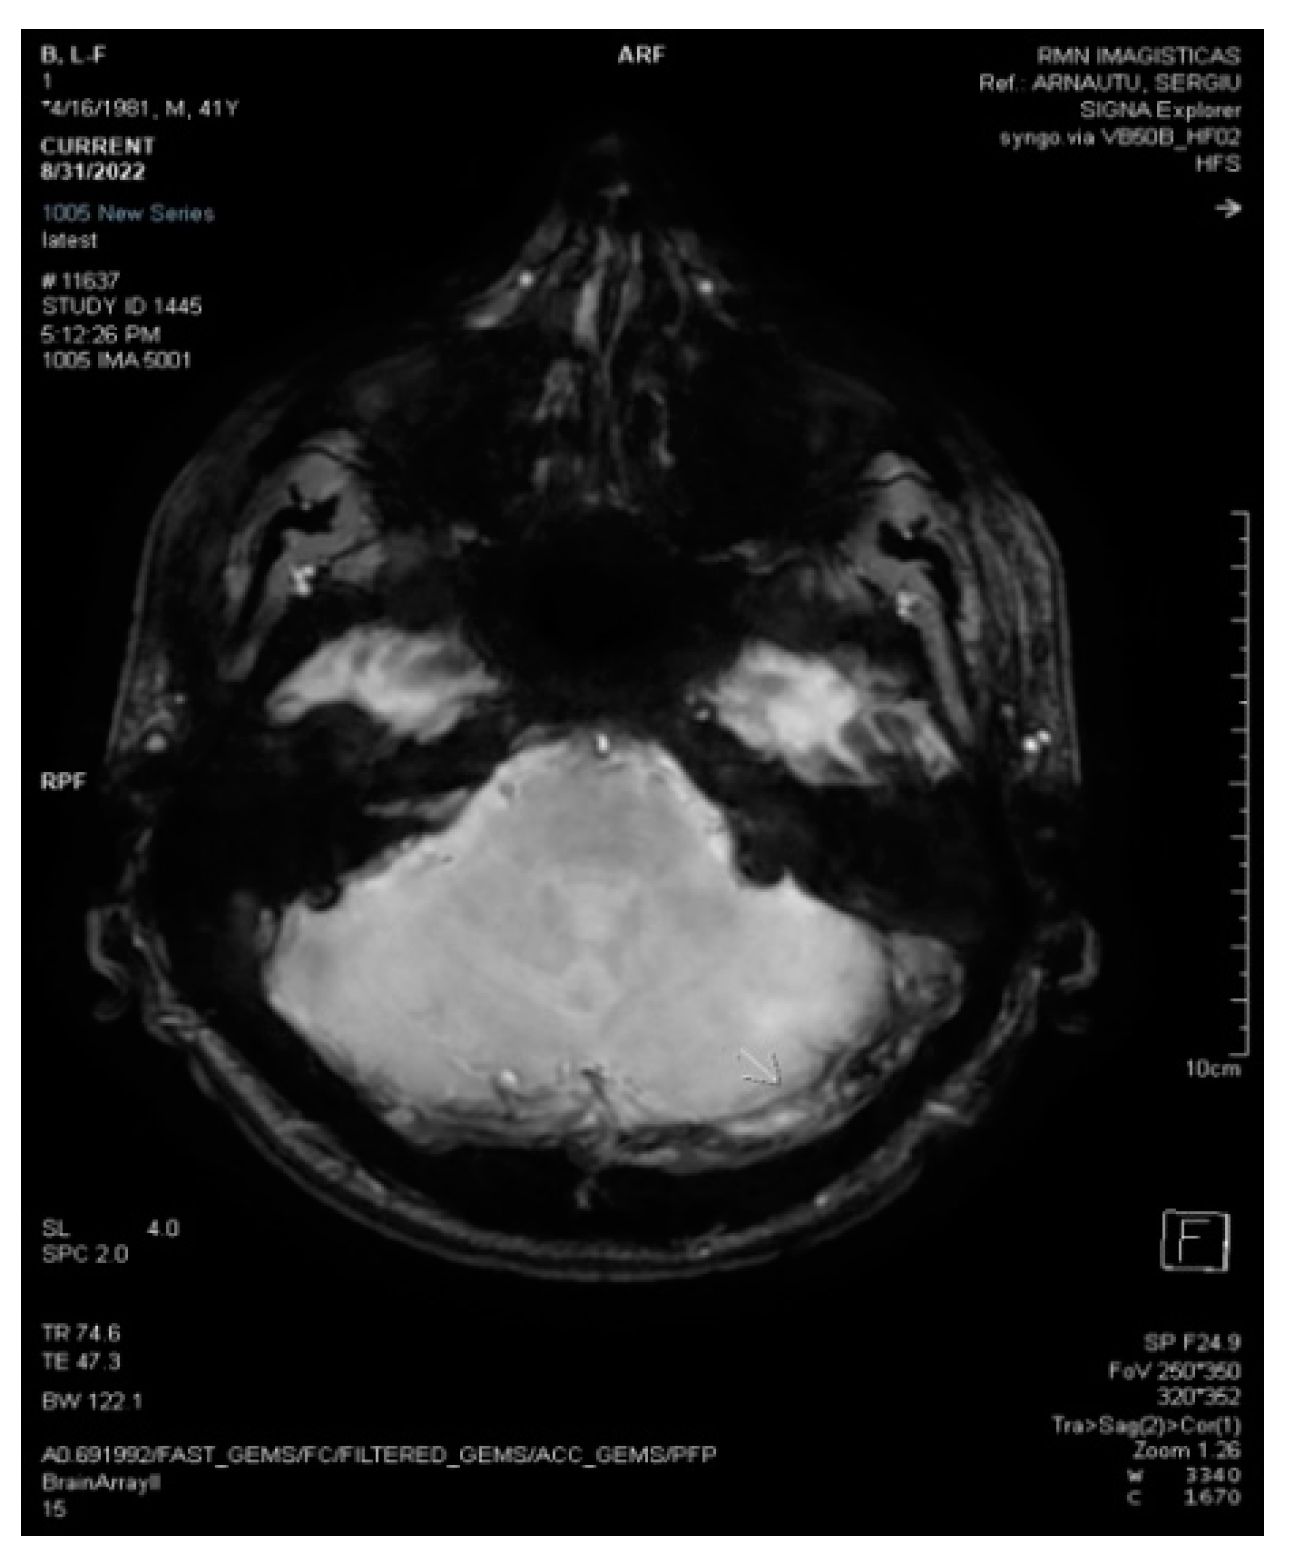

2.2. Neuroimaging Data